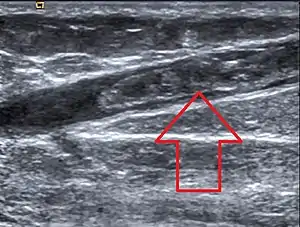

Тромбофлебіт

Тромбофлебі́т — утворення згустка крові, меншого за розміром ніж внутрішній просвіт судини, на внутрішній стінці вени, що викликає запалення. Якщо паталогічний процес не зупиняти, відбувається закупорювання вени згустком крові, (тромбом) та появляються нові ділянки в судинні, де повторюється усе перераховане. Найчастіше спостерігають тромбофлебіт нижніх кінцівок.

Клінічні ознаки

Тупий, витягувальний біль в ураженій кінцівці. При огляді: різний ступінь набряку кінцівки, рожеві або червоні смуги за ходом запалених підшкірних вен, при пальпації — твердоеластичні округлі ущільнення різного розміру, різко болючі.